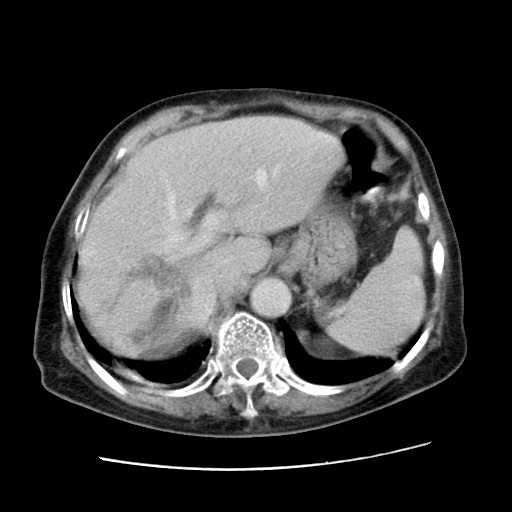

女,77.无不适

肝脏变异、异位胆囊,肝右叶肝内胆管结石并肝内胆管扩张。

肝右叶肝内胆管结石并肝内胆管扩张。

肝右叶肝内胆管结石并肝内胆管扩张

胆总管扩张

肝右叶肝内胆管结石并肝内胆管扩张。胆总管下段梗阻,考虑壶腹部占位。

右侧肝内胆管局限性扩张,其内密度不均匀,扩张的胆管壁增厚,考虑肝内胆管炎合并结石可能性大

肝右叶肝内胆管结石并肝内胆管扩张。胆总管下段梗阻,考虑壶腹部占位。支持